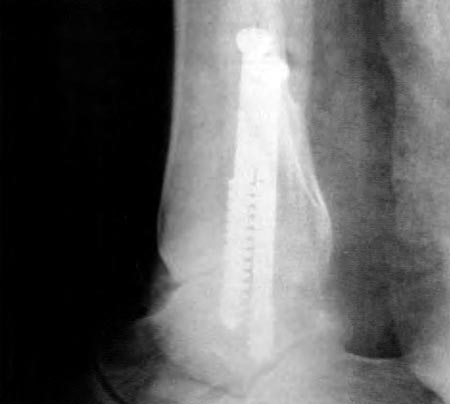

La causa más frecuente de artrosis fue la postraumática (diez casos).(Fig. 1) Otras etiologías fueron Artritis Reumatoidea en dos casos, artropatía hemofílica dos tobillos en un paciente, secuela de poliomielitis un caso, osteocondrítis de astrágalo un caso.

Figura 1 a: Rx de tobillo con osteosíntesis

Figura 1 b: artrosis secundaria 2 años después